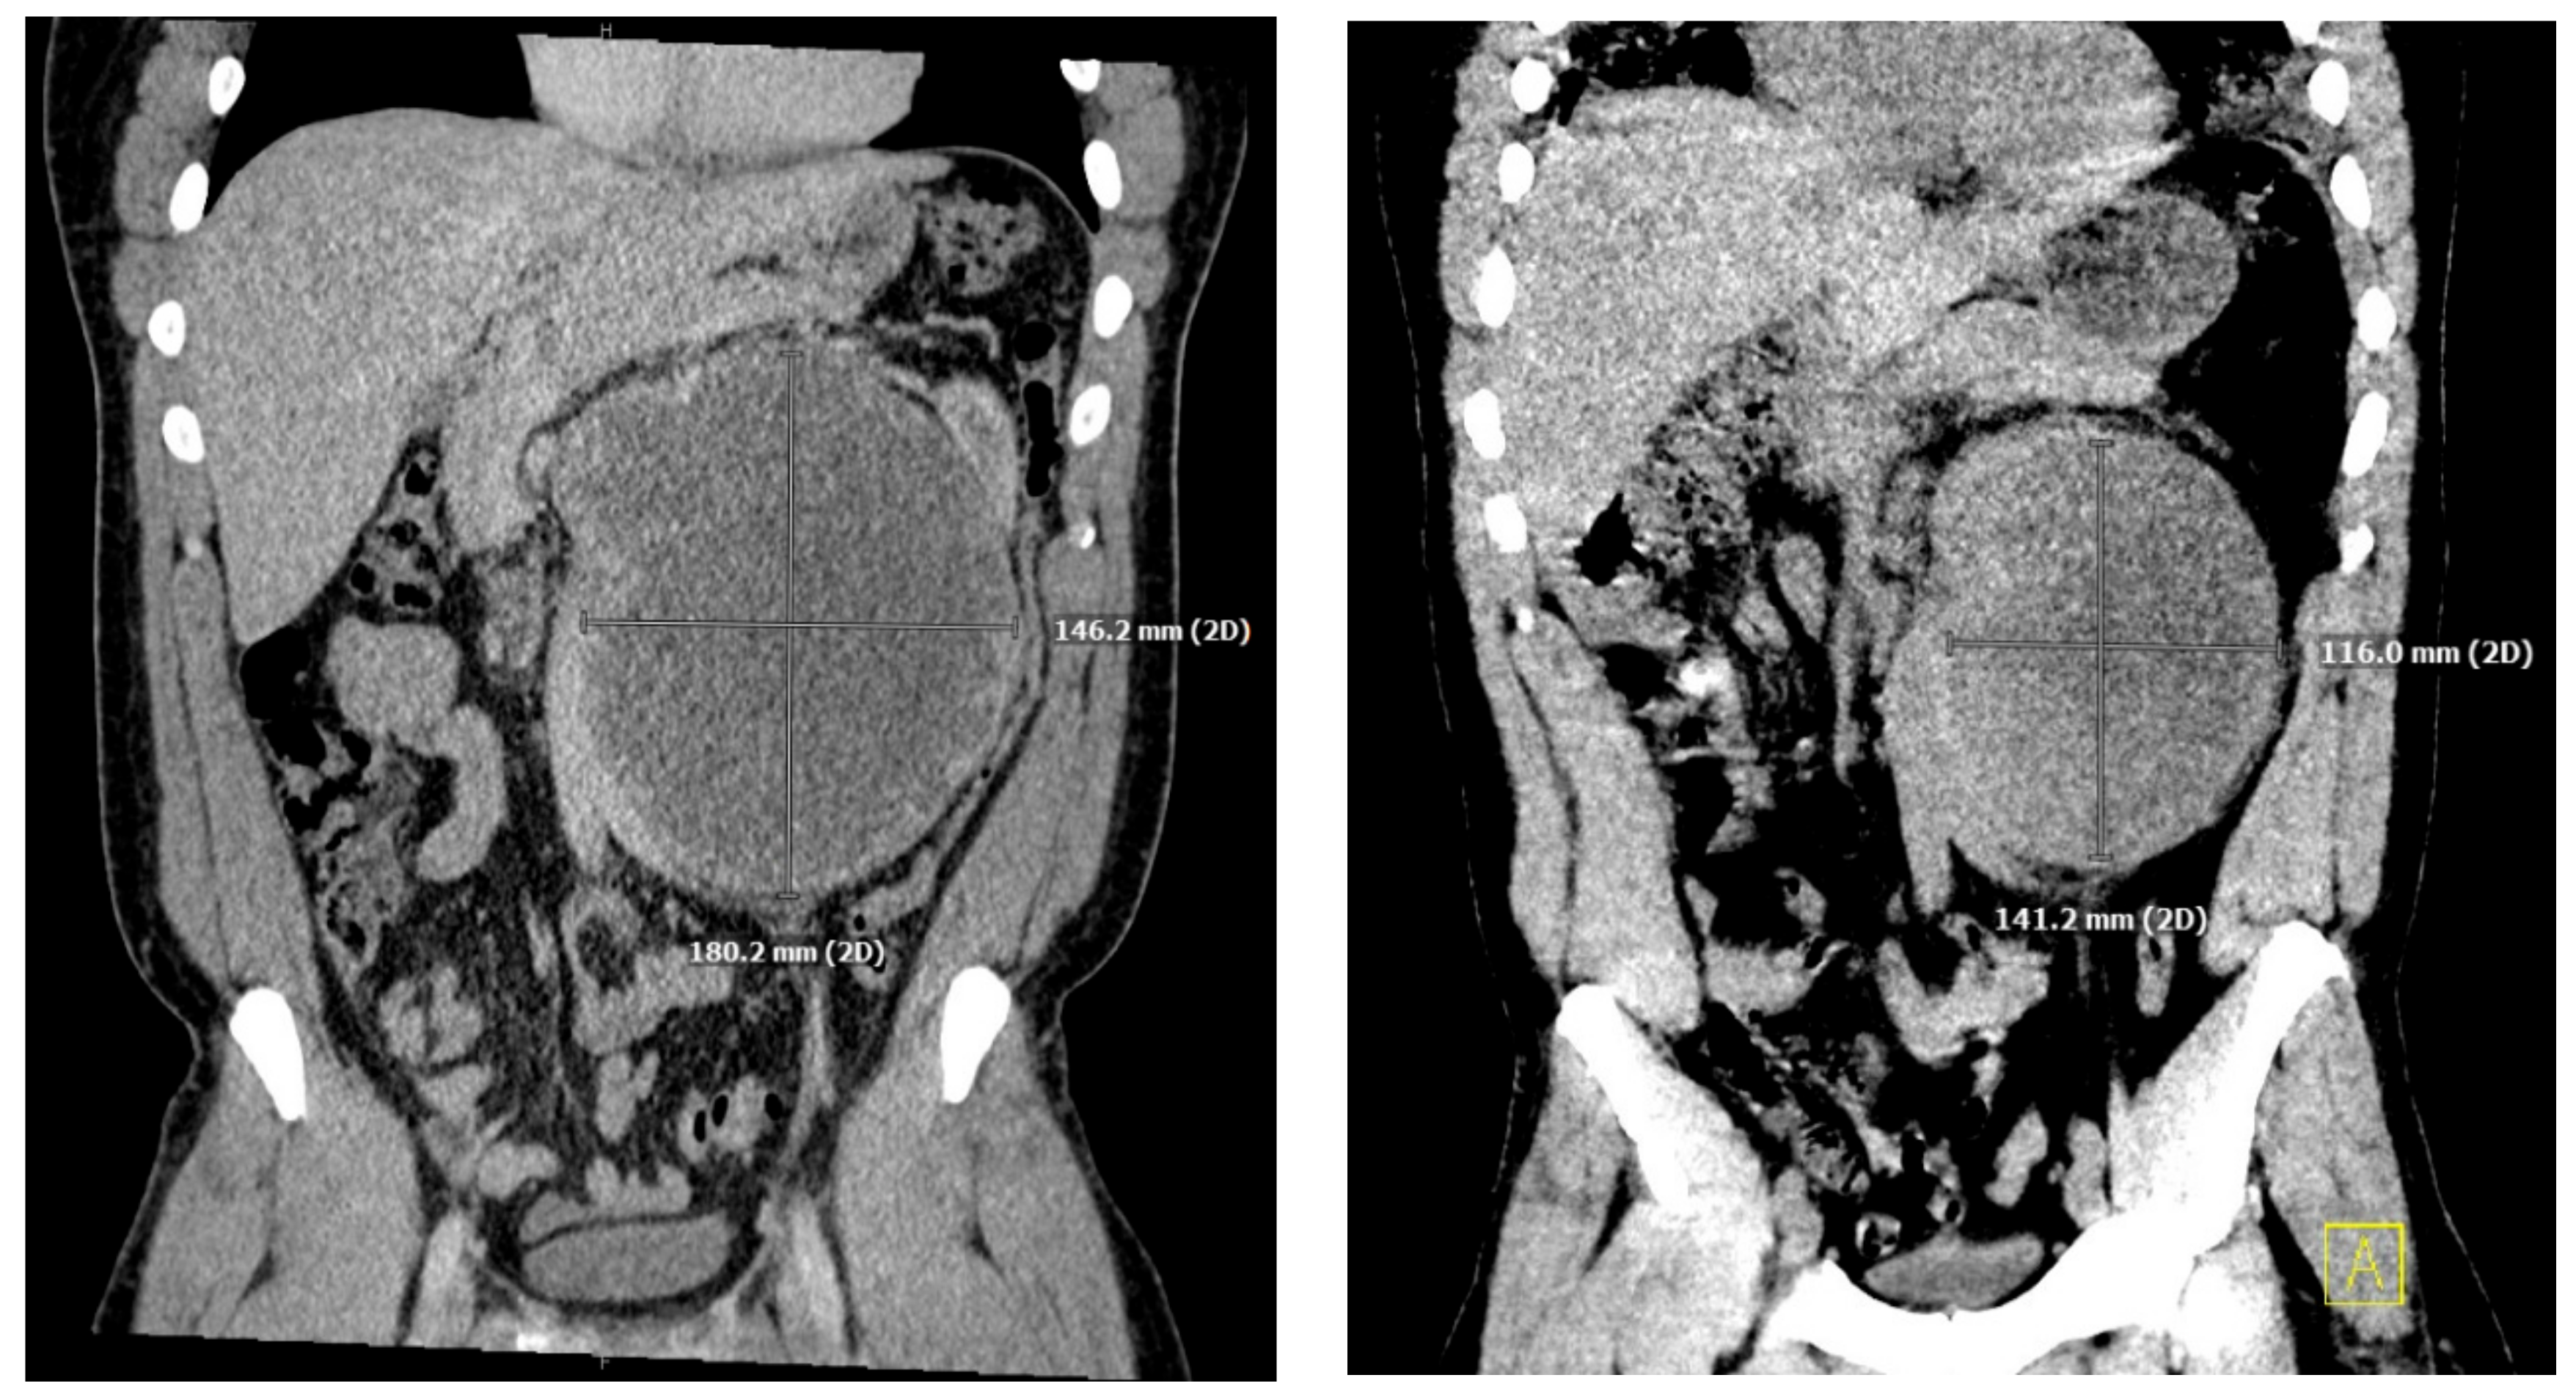

He underwent an orchiectomy of the left testis and received a total of four cycles of etoposide, bleomycin, and cisplatin over the ensuing three months. The tumor was responsive to chemotherapy showing a significant decrease in hCG levels from 75,005 IU/L to 149 IU/L and shrinking of the retroperitoneal mass (Figure 1).

Figure 1.

Coronal slices of CT images performed immediately after diagnosis of retroperitoneal mass (left) originally measuring 18 × 14 cm, and three months after initiation of treatment (right) measuring 14 × 12 cm.

One month after finishing the last cycle of chemotherapy, the patient developed shortness of breath and a dry cough and was diagnosed with pneumonia, requiring readmission to the hospital. His initial oxygen saturation on room air was as low as 90%. He was given supplemental oxygen, ceftriaxone, and azithromycin. A CT scan revealed ground glass opacities and air bronchograms and re-demonstrated his retroperitoneal mass and liver lesion, both significantly smaller (Figure 1 and Figure 2).